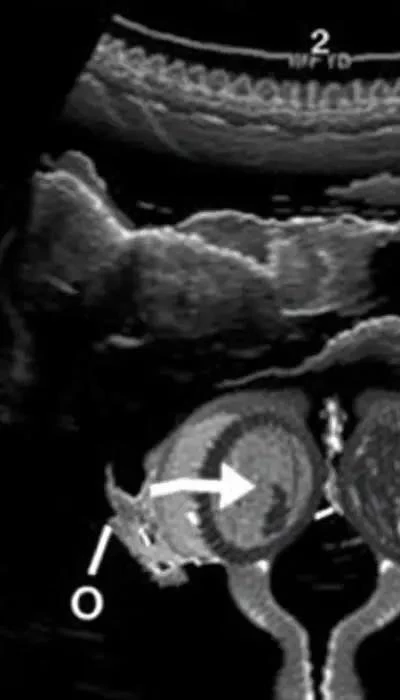

Ультразвуковое исследование (УЗИ) органов малого таза – один из наиболее информативных методов диагностики аднексита. УЗИ позволяет оценить состояние яичников и маточных труб, выявить признаки воспаления, такие как увеличение размеров придатков, наличие свободной жидкости в брюшной полости и утолщение стенок маточных труб. Допплерография позволяет оценить кровоток в придатках матки.